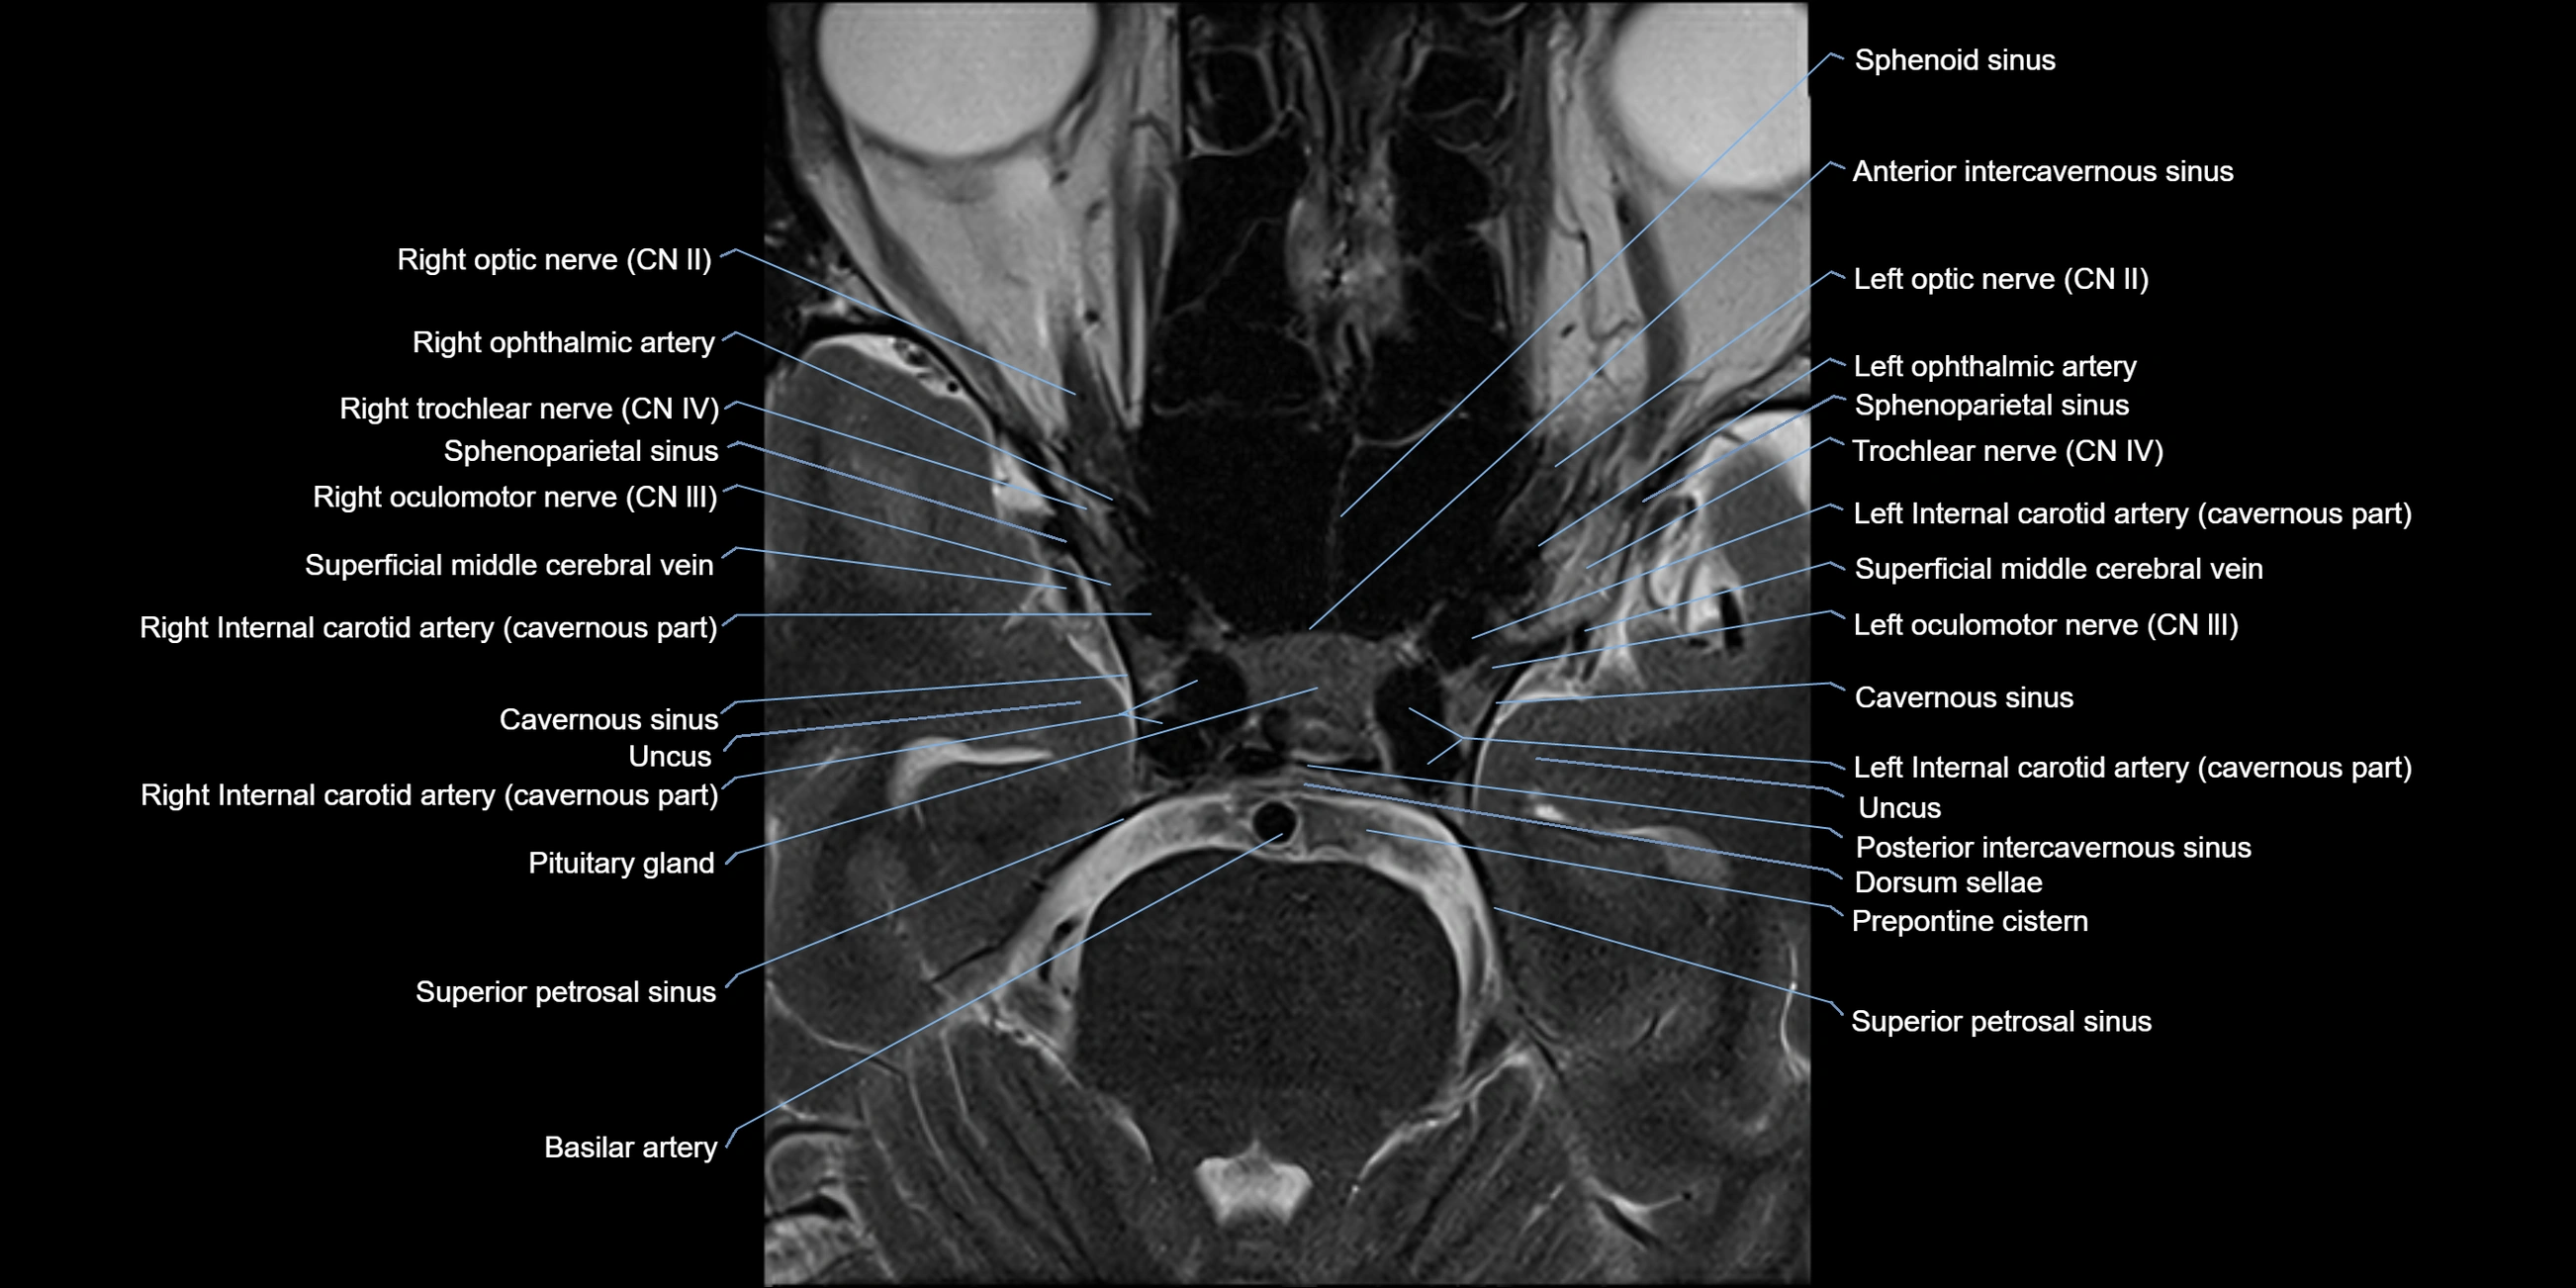

MRI Appearance

The abducens nerve is a small, thin, linear structure

Best visualized on high-resolution T2-weighted 3D MRI sequences (e.g., FIESTA or CISS)

Seen as a hypointense (dark) line running from the brainstem at the pontomedullary junction, traversing the prepontine cistern, and entering Dorello’s canal under the petrosphenoidal ligament, then into the cavernous sinus, and finally the orbit

May be challenging to visualize in standard MRI due to its small size

Pathology may be inferred by absence, displacement, or enhancement of the nerve

MRI images